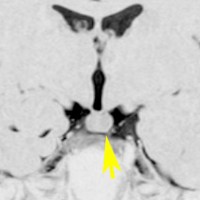

小さな典型的な視床下部過誤腫

無症候で発見されたpedunculated typeです。視床下部の底面からぶら下がるようにしてあります。左のCISS画像で形がよくわかります。中央のT1では灰白質と等信号です。右のT2では高信号となっています。

乳頭体(矢印)からは離れているタイプです。ですから笑い発作を生じません。右側のガドリニウム増強画像ではまったく増強されていないのが特徴です。